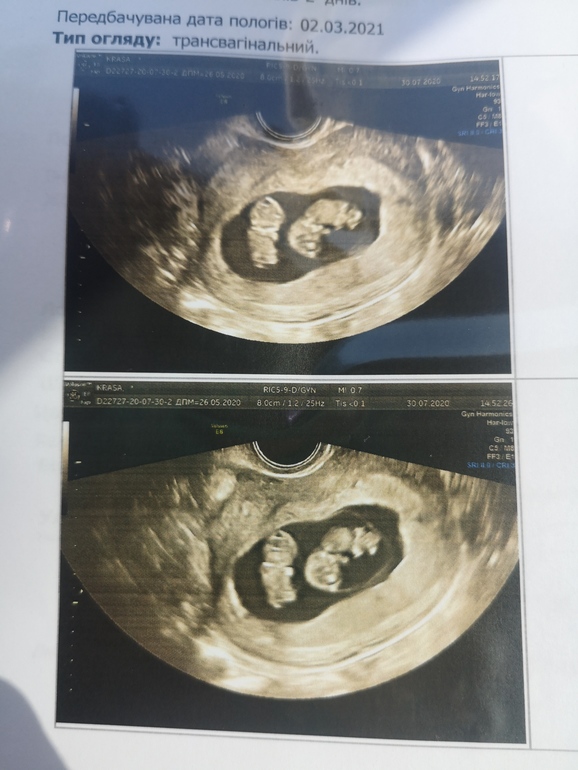

Спасибо🥰Ето было 8недель и 3дня. Но еще на 6 неделе нам показали одного ембриончика. Так что все возможно 🤷‍♀️👍🥰💋

Какие прекрасные крошки в одном яичке) чудо чудесное! Будьте здоровенькими ❤️

Спасибо 💋. У меня сейчас 9.3. Ето не оба остались, а один поделился.У меня моно ди двойня.